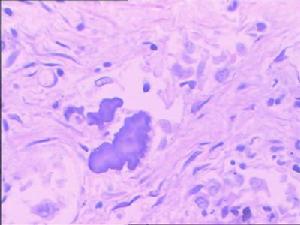

肺切面上的微小(大米粒)白色結節流行病學

肺切面上的微小(大米粒)白色結節生理